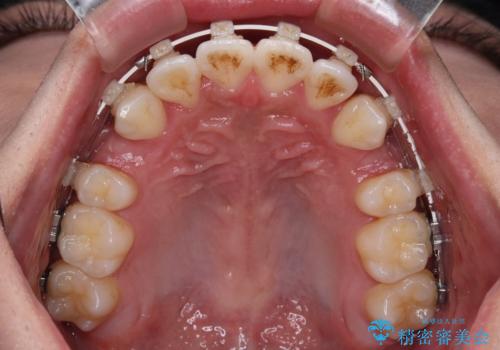

- 矯正装置

- 審美装置

- 八重歯と口元の閉じにくさを気にして来院された患者様です。

非抜歯矯正で歯列を整えると、治療後に口元が今よりも突出する可能性が高かったため、上下左右の第一小臼歯4本を抜歯し、ワイヤー装置にて矯正治療を行うこととしました。

- 治療中は歯磨きがしにくくなるため、虫歯や歯周病になりやすくなります